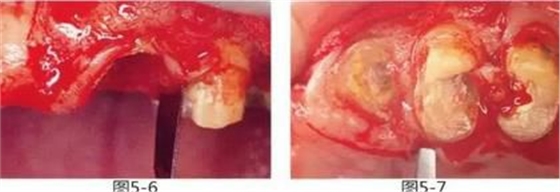

圖5-6,7

使用手術(shù)刀、7號(hào)牙齦刀、11號(hào)牙齦刀、咬骨鉗,盡可能將牙根周圍的軟組織進(jìn)行整體切除。